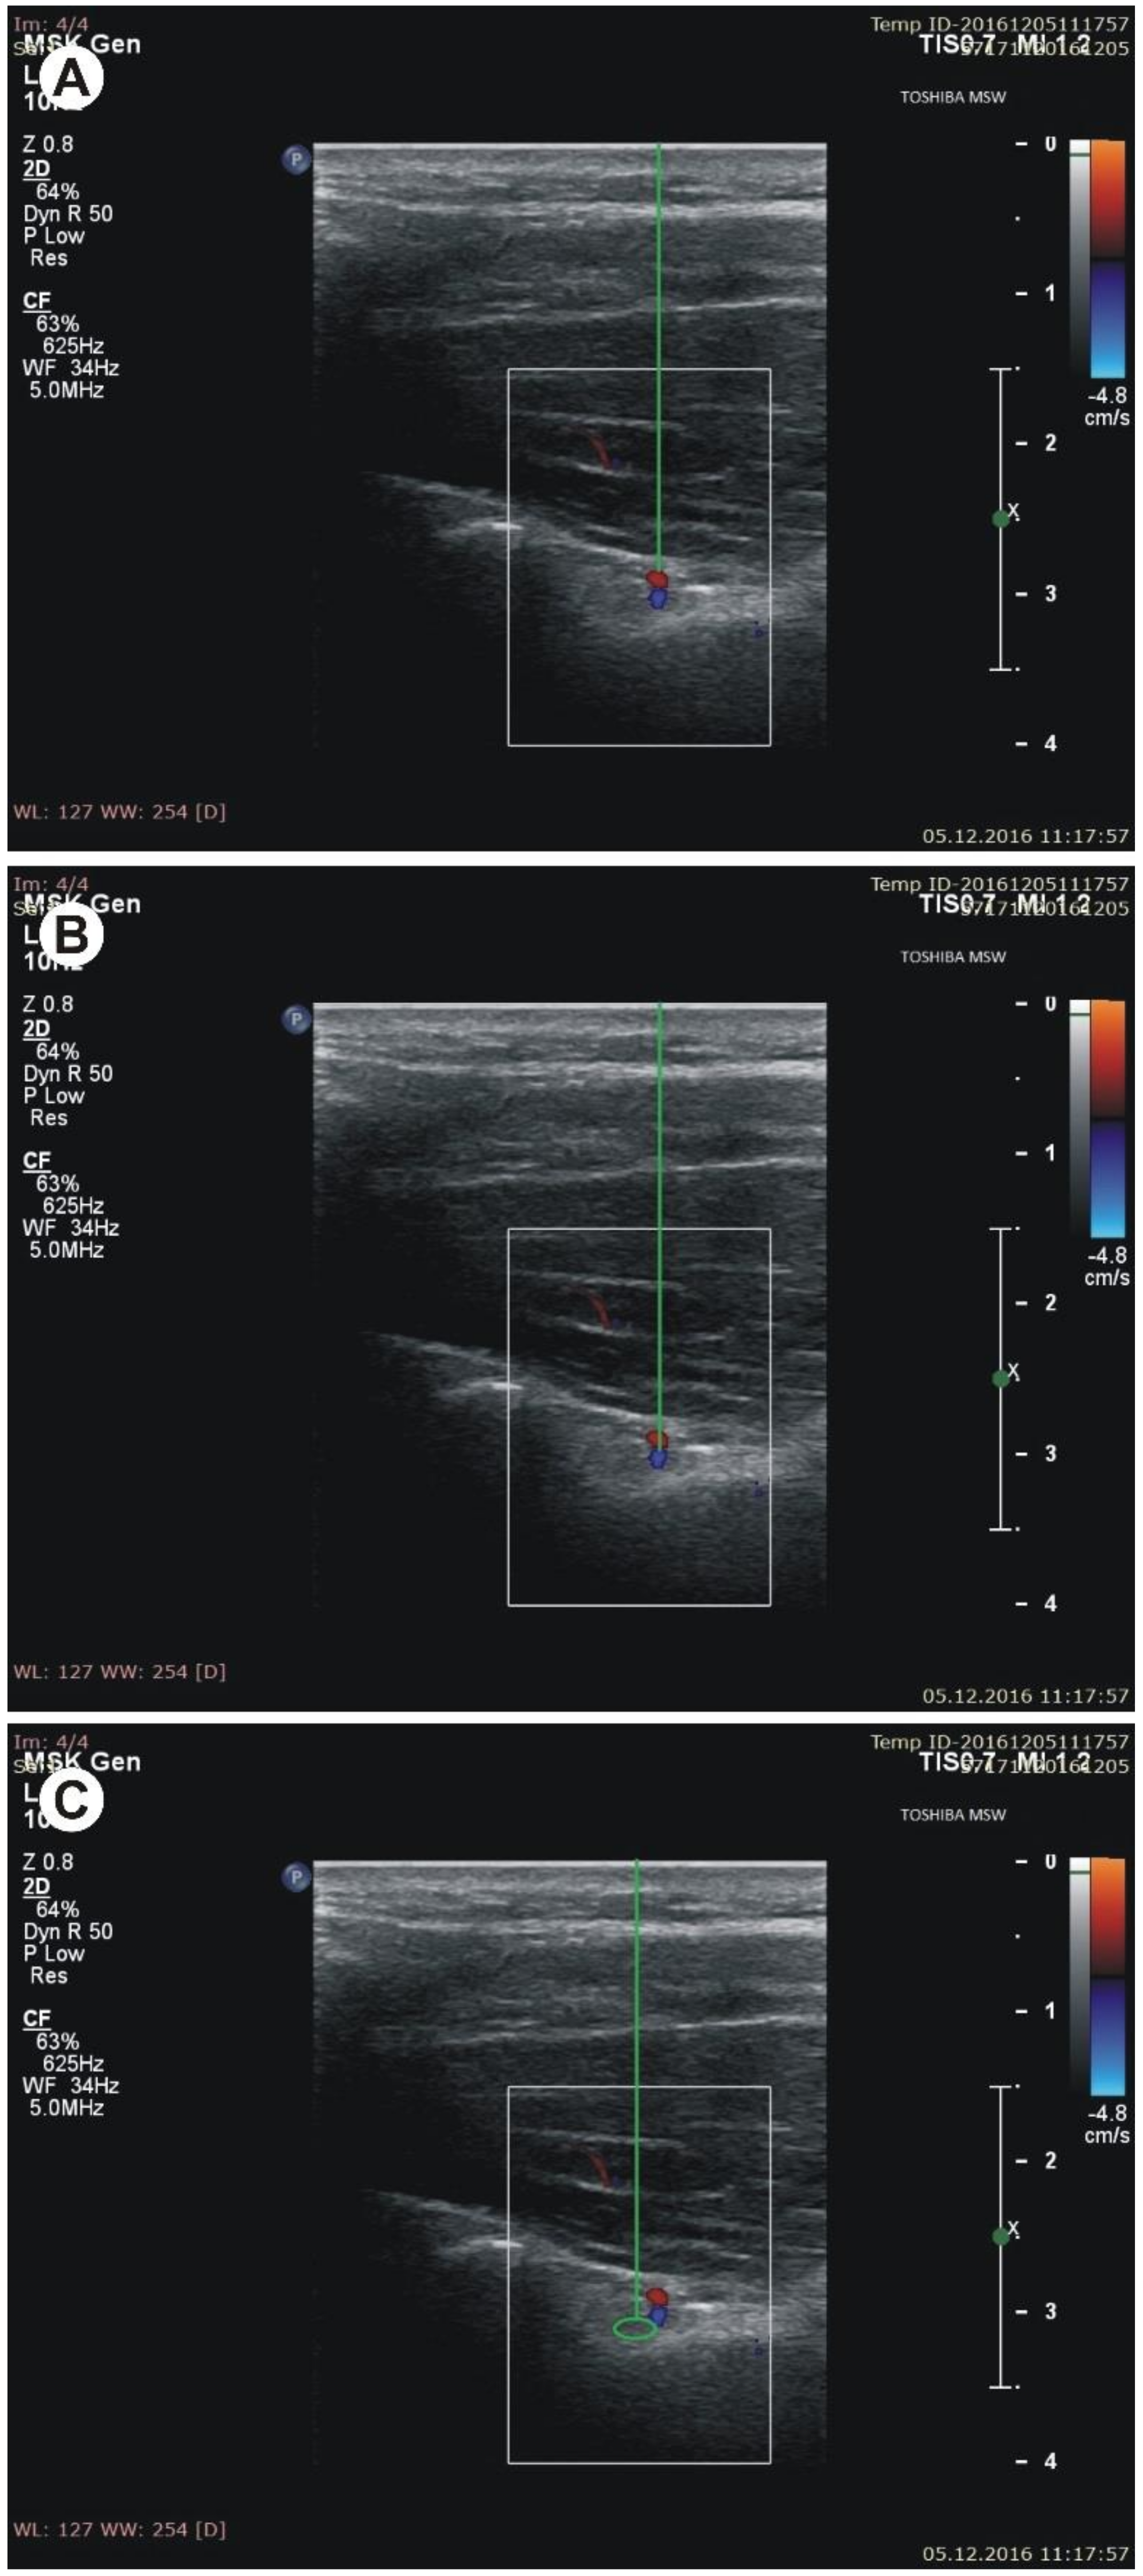

Figure 4. Measurements of the suprascapular notch region during ultrasonographic investigation. (A) the thickness of the soft tissue over the suprascapular artery; (B) the thickness of the soft tissue over the suprascapular vein; (C) the thickness of the soft tissue over the suprascapular nerve. - (g)

- the thickness of the soft tissue over the suprascapular artery: the minimal distance between the suprascapular artery and the skin (Figure 4A)

- the thickness of the soft tissue over the suprascapular vein: the minimal distance between the suprascapular vein and the skin (Figure 4B)

- the thickness of the soft tissue over the suprascapular nerve: the minimal distance between the suprascapular nerve and the skin (Figure 4C).